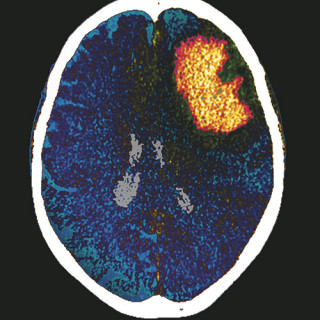

Brukere av psykedelika har ikke dårligere psykisk helse enn andre. Forskere fra Norges teknisk-naturvitenskapelige universitet har analysert data fra en amerikansk befolkningsstudie der et representativt utvalg av den voksne befolkningen ble bedt om å svare på spørsmål rundt eget rusforbruk og psykisk helse (1). Blant de om lag 130 000 som svarte, hadde nesten 22 000, dvs. over 13 %, prøvd LSD, psilocybin, meskalin eller peyote i løpet av livet. Blant disse var det en overvekt av unge, ugifte menn av hvit eller blandet herkomst med høyere utdanning og god økonomi. Det var ingen sammenheng...